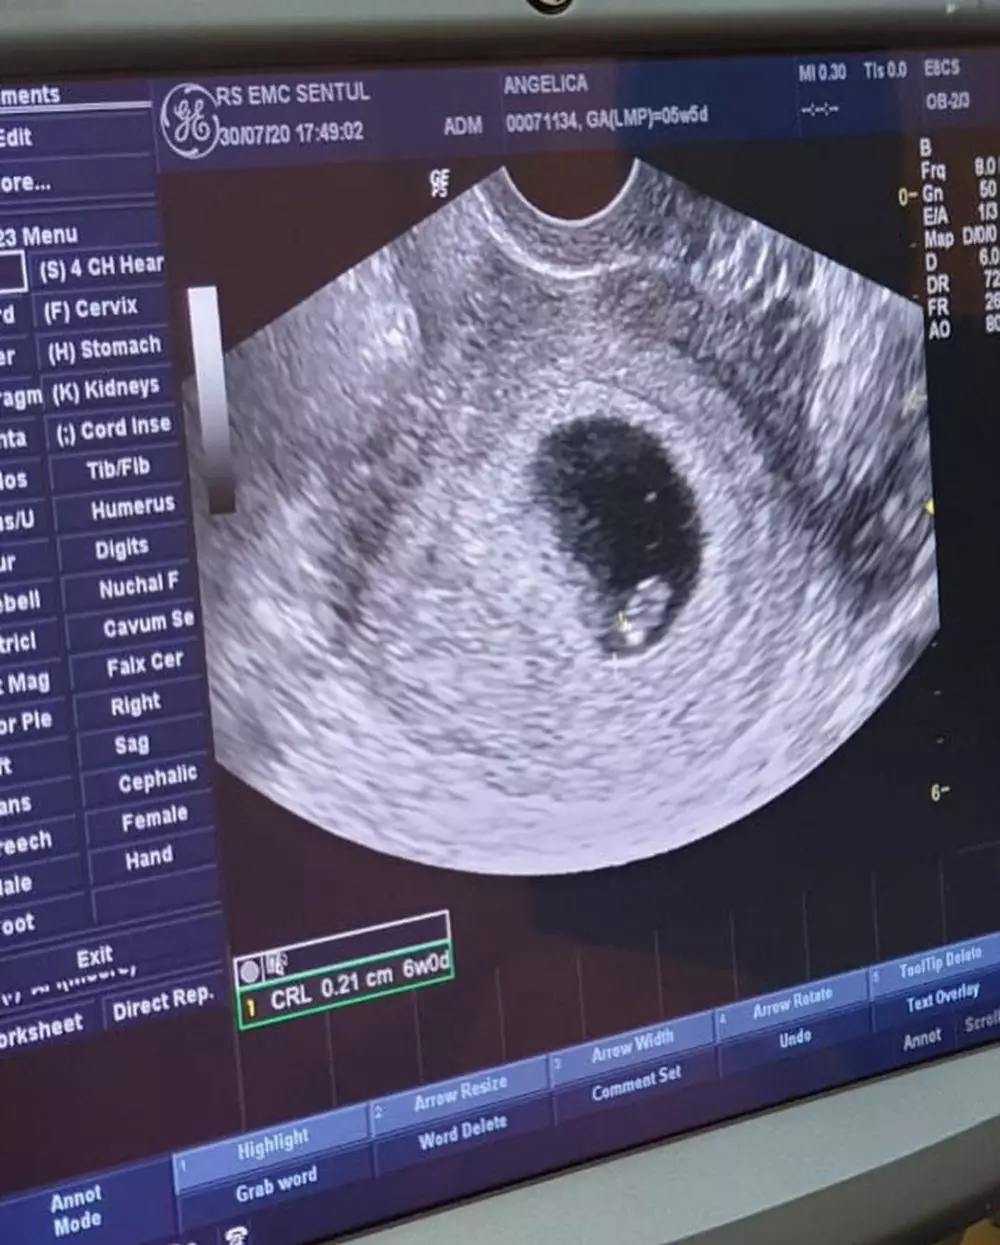

Lewat sebuah unggahan di akun Instagram-nya, Angelica lantas memamerkan foto USG sang janin. Ia pun merasa bersyukur karena memiliki kesempatan untuk hamil secepat itu.

foto: Instagram/@angelicasimp.new